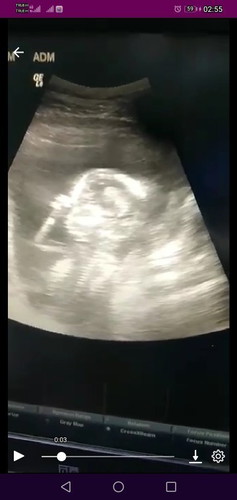

สอบถามแม่ๆหน่อยค่ะ ตั้งครรภ์ท้องแรก มีแต่คนทักว่าผอมลง แต่รู้สึกว่าตัวเองกินเยอะมาก มีแต่คนบอกว่าท้องไม่เหมือน3เดือน อายุครรภ์พึ่ง12สัปดาห์1วัน กลัวลูกตัวเล็กมากค่ะเพราะน้ำหนักแม่ลง อาการแพ้ท้องจะเป็นแบบช่วงๆ ไม่เยอะเหมือนตั้งครรภ์แรกๆ อยากถามแม่ๆว่า กินอะไร ลูกถึงจะได้สารอาหารครบถ้วนค่ะ และกินอะไรน้ำหนักตัวแม่ถึงจะขึ้นค่ะ #ขอคำแนะนำหน่อยค่ะ #ท้องแรกคะ #ขอบคุณสำหรับคำตอบค่ะ